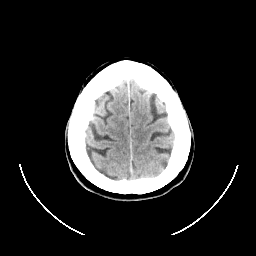

CT Study #1 -- Slice #25